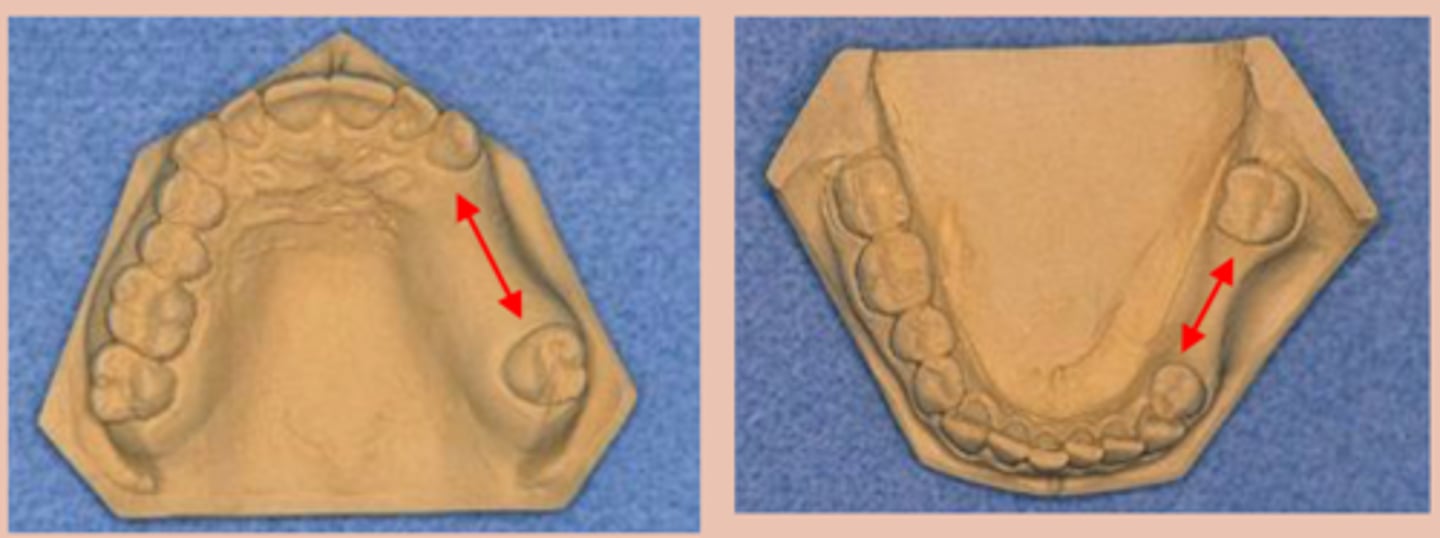

Tooth supported:

A unilateral edentulous area with natural teeth both anterior and posterior to the area

Tooth and tissue supported, tooth supported:

A single but bilateral (crossing the midline) edentulous area located anterior to the remaining natural teeth